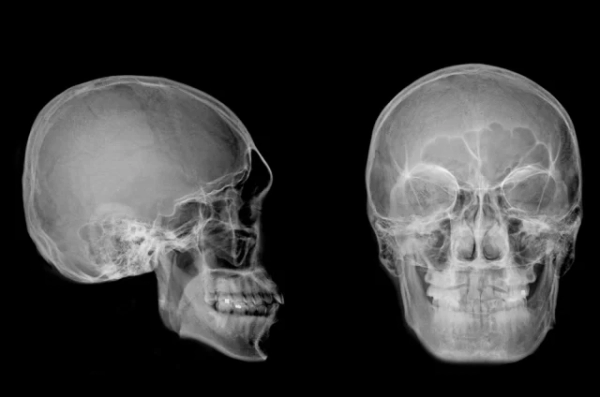

Компьютерную томографию провели в Лаборатории ядерной и инновационной медицины физического факультета Новосибирского государственного университета. Томограф позволил виртуально «удалить» эти покровы и создать точную цифровую, а затем и физическую 3D-модель черепа.

Так удалось узнать, что женщина при жизни получила серьёзную травму головы. Возможно, упала с лошади или с высоты. Диагноз, поставленный спустя тысячелетия, оказался шокирующим: разрушенный правый височно-нижнечелюстной сустав, смещение и подвывих нижней челюсти с повреждением связок. После такой травмы несчастная не могла ни есть, ни говорить. В общем, её ждала неминуемая и мучительная гибель. Но древние врачи, видимо, рассудили иначе.

После того как была создана 3D-модель черепа, за её изучение взялся доктор медицинских наук, рентгенолог Андрей Летягин. Он обнаружил нечто невероятное — следы сложной хирургической операции с протезированием разрушенного сустава. Специалист увидел два тонких искусственных канала диаметром 1,53 миллиметра, просверленных в кости нижней челюсти. Внутри каналов сохранились остатки эластичного материала — предположительно, конского волоса или сухожилия животного. Это была примитивная конструкция, которая удерживала суставные поверхности вместе и позволяла женщине двигать челюстью. То есть сустав работал!

«Скорее всего, во время операции пациентка держала рот раскрытым, — рассуждает Андрей Летягин. — Просверливали эти каналы, вероятно, в два этапа — в горизонтальном и вертикальном направлениях. На КТ-изображениях было явно видно, что кость просверлена очень ровно, а вокруг отверстий наросла костная ткань. Выявленное кольцевое уплотнение костной ткани указывает на прижизненное происхождение этих каналов».